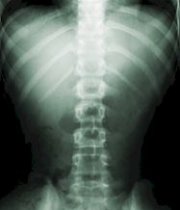

Un equipo de investigadores de la Universidad Cheng Kung de Taiwán ha descubierto que la proteína interleukin (IL-20) es clave para el tratamiento de la osteoporosis, que afecta a los huesos.

Los investigadores descubrieron que los enfermos de osteoporosis tenían concentraciones de IL-20 en la sangre mayores de lo normal, lo que parece señalar que esta proteína está ligada al progreso de la afección.